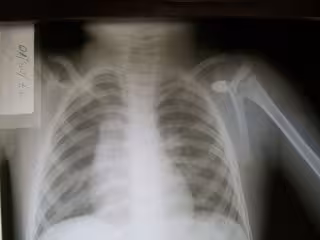

Radiografía, rayos X, radiología, técnicas de imagen

BOBJGALINDO / WIKIMEDIA COMMONS